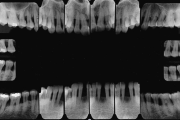

Krooniline parodontiit

Krooniline parodontiit on mikroobide poolt põhjustatud hammaste tugikudede põletik, mille tulemusena tekib progresseeruv alveolaarluu (nähtav röntgenograamil) ja periodontaalligamendi destruktsioon, igemetaskute moodustumine, igeme retsessioon või mõlemad kahjustused kombineeritult. … Loe edasi »

- luu destruktsioon (5)

- vertikaalne luukadu (2)

- horisontaalne luukadu (3)